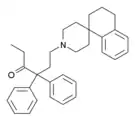

The pharmacodynamic response to an opioid depends upon the receptor to which it binds, its affinity for that receptor, and whether the opioid is an agonist or an antagonist. For example, the supraspinal analgesic properties of the opioid agonist morphine are mediated by activation of the μ1 receptor; respiratory depression and physical dependence by the μ2 receptor; and sedation and spinal analgesia by the κ receptor. Each group of opioid receptors elicits a distinct set of neurological responses, with the receptor subtypes (such as μ1 and μ2 for example) providing even more [measurably] specific responses. Unique to each opioid is its distinct binding affinity to the various classes of opioid receptors (e.g. the μ, κ, and δ opioid receptors are activated at different magnitudes according to the specific receptor binding affinities of the opioid). For example, the opiate alkaloid morphine exhibits high-affinity binding to the μ-opioid receptor, while ketazocine exhibits high affinity to ĸ receptors. It is this combinatorial mechanism that allows for such a wide class of opioids and molecular designs to exist, each with its own unique effect profile. Their individual molecular structure is also responsible for their different duration of action, whereby metabolic breakdown (such as N-dealkylation) is responsible for opioid metabolism.

Anilidopiperidines

Phenylpiperidines

Diphenylpropylamine derivatives